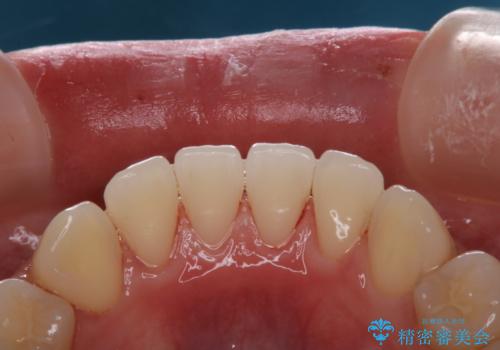

PMTCを行う際には担当の歯科衛生士が、患者様1人1人の虫歯・歯周病などのリスク・ブラッシングスキルなどを確認します。

単なる磨き方の指導だけではなく、歯並びや歯肉の状態、ライフスタイルなどにより、患者様に適した歯ブラシや歯磨剤の選択をしたり、お口のお悩みについてのご相談も承っております。

日々の磨き残しや唾液の成分などによりバイオフィルムや歯石はどうしても付着してしまいます。歯石や汚れを放置していると、そこで病原菌が繁殖す始めます。歯肉に炎症が生じると歯周病などの引き金となります。

そのため、2~3か月に1回は、歯科医院での専門的クリーニングをすることが大切です。